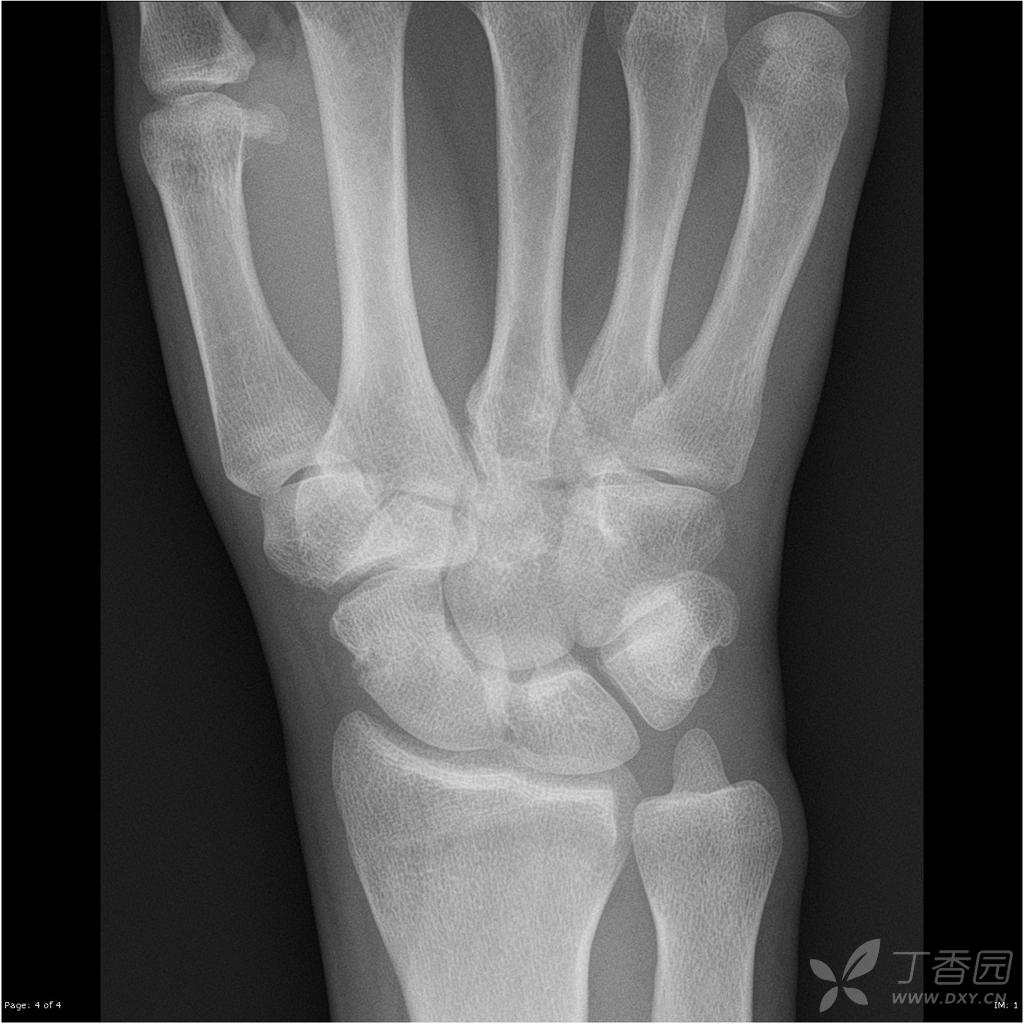

求助腕关节有骨折吗

【读片】单侧腕关节肿痛,不能屈曲月余.公布结果. [病例帖]